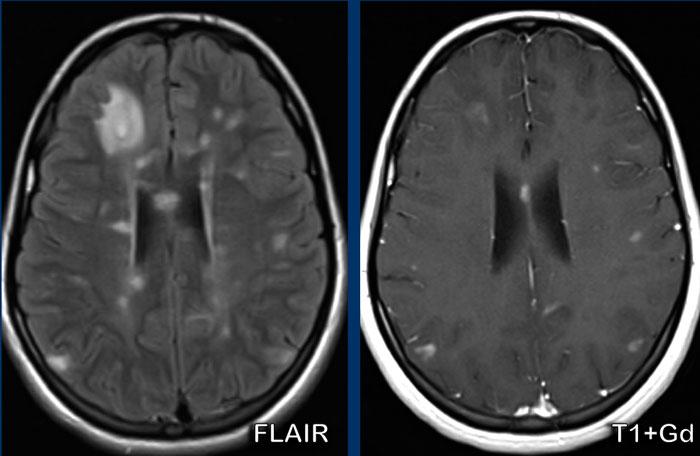

Bệnh nhân này đã được chẩn đoán xơ cứng rải rác (MS).

Chú ý rằng một số tổn thương tăng tín hiệu trên ảnh FLAIR có ngấm thuốc trên ảnh T1W+Gd, đây là dấu hiệu của bệnh đang hoạt động.

Các tổn thương ngấm thuốc thể hiện các kiểu ngấm thuốc khác nhau: dạng nốt và dạng vòng nhẫn (không hoàn toàn).

Các tổn thương cũng nằm ở thể chai.

Đây không phải là vị trí thường gặp của di căn não hay thiếu máu cục bộ, nhưng thường thấy trong MS.

Vị trí các bất thường trên FLAIR vuông góc với não thất (ngón tay Dawson), vị trí cạnh vỏ não của các tổn thương chất trắng và kiểu ngấm thuốc không hoàn toàn giúp gợi ý chẩn đoán bệnh mất myelin, tức là MS là khả năng nhất.